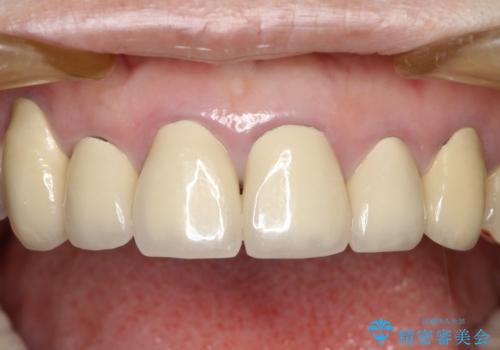

- 下顎の前歯に激痛を覚えて来院された患者様です。

取り急ぎ下顎前歯数歯の根管治療を、銀座しらゆり歯科医院長の林先生にお願いし、それ以外に気になっている、不自然な色調のクラウン、金属部分が見えてブラッシングがしにくいインプラント補綴、口元の突出感、出血のしやすい歯周ポケットなど、全てを解決するための治療を行うこととしました。

期間と費用はかかりましたが、気になっていた部分全てを改善でき、患者様には大変満足していただきました。